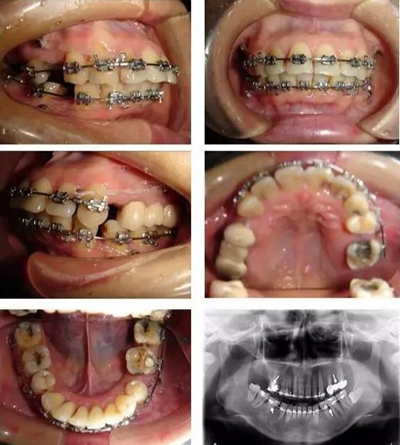

▲ 圖3 矯治中,利用微種植體支抗內(nèi)收前牙時的牙(牙合)像及曲面斷層片